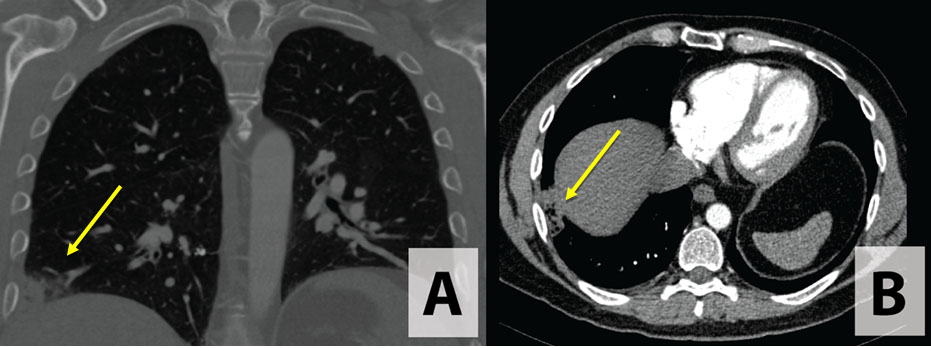

A 50-year-old non-smoking male history of basal cell carcinoma (BCC) status post-excision and gastroesophageal reflux disease (GERD) presented to urgent care with fatigue, shortness of breath (SOB), and right shoulder pain for one day. The patient was prescribed diazepam and a muscle relaxant for shoulder pain. Chest X-ray (CXR) noted a small pleural effusion on right lower lobe, and the patient was prescribed prednisone (six day course) with instructions for follow-up. Four days following this visit, the patient was seen by his primary care physician describing SOB, fatigue, and loss of appetite. The pain was noted to be intermittent and pleuritic. The patient denied any related fever, myalgia, headache, sick contacts, or hemoptysis. He described recently worsening GERD with nighttime awakenings with a sour taste in the back of his throat. As labs revealed elevated D-dimer and repeat CXR noted an ill-defined wedge like opacity in the right lower lobe (Figure 1), computed tomography (CT) chest with contrast was performed. Computed tomography chest revealed a 4 × 1.4 cm collection of fluid and gas at the lateral segment of the right lower lobe with surrounding stranding and edema (Figure 2). Differential diagnosis considered caseating abscess or necrotic tumor. The patient denied coughing, recent travel, no significant occupational, recreational exposures, or sick contacts.

Figure 2: CT chest with contrast demonstrating a collection of fluid and gas at the lateral segment of the right lower lobe: (A) coronal and (B) transverse.